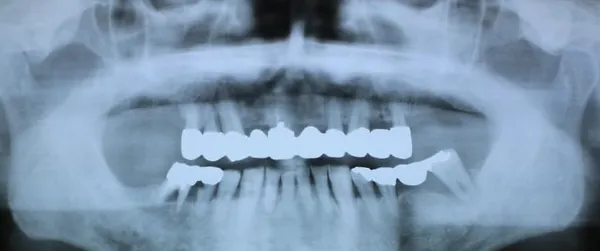

6入れ歯にしないブリッジ治療【ケース2】

H14.12.25のレントゲン

上の歯13本のうち、治療不可能な歯を3本抜き右端から左端までつなげたブリッジを作りました。

H16.1.16に上の歯(ブリッジ)が完成しました。

上の写真は15年以上経過した令和1年11月6日に撮影した写真で経過良好と思われます。